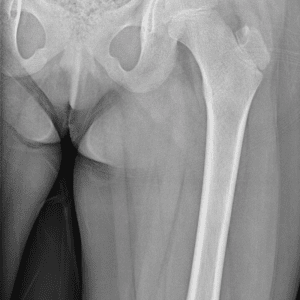

Pediatric Radiographs